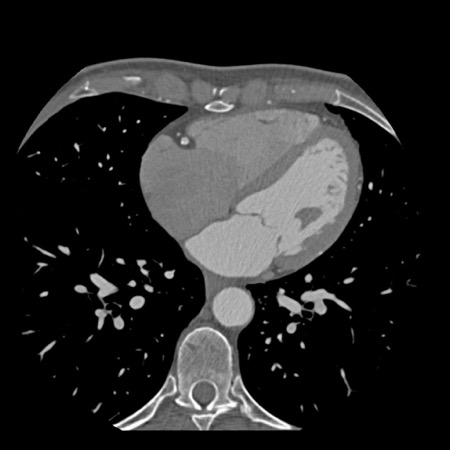

case 4 – CAD-RADS 3/P1/I+ thrombus left ventricle

First, scroll through the CTA images.

How would you describe the findings on the coronary CTA?

The findings are:

- Moderate (50-69%)

stenosis in the proximal LAD caused by a non-calcified plaque. - Variant of

sinoatrial (SA) nodal artery. The artery usually arises from the RCA as a second

branch after the conus artery, however in this case it arises from the LCX,

courses behind the aorta, anastomosing with the right atrium and with a small

branch supplies the SA-node of the heart. - Thrombus in the

apex of the left ventricle. - CTP was performed

in this patient. CTP showed a perfusion defect at stress imaging in the

territory of the LAD (I+), at rest no perfusion defect was visible.

This patient classifies as CAD-RADS 3/P1/I+, which means

this patient requires further investigation.